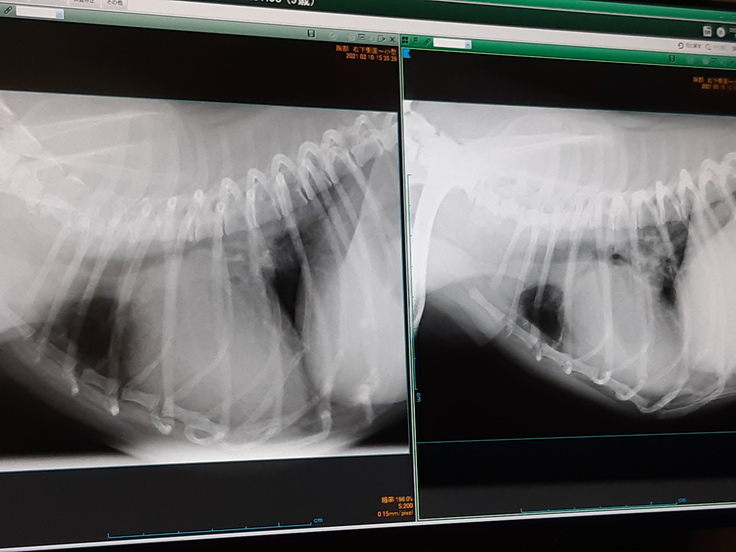

左が手術前で右が土曜日です、上まで肥大していた心臓が小さくなっています。

しかし、手術の影響で前から言ってます左の肺がまだ正常に戻っていません。

ちょっとショックですね、左の肺が白くなってる部分があり小さくなってます。